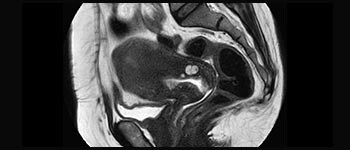

Enhanced diagnostic confidence in neuro oncology